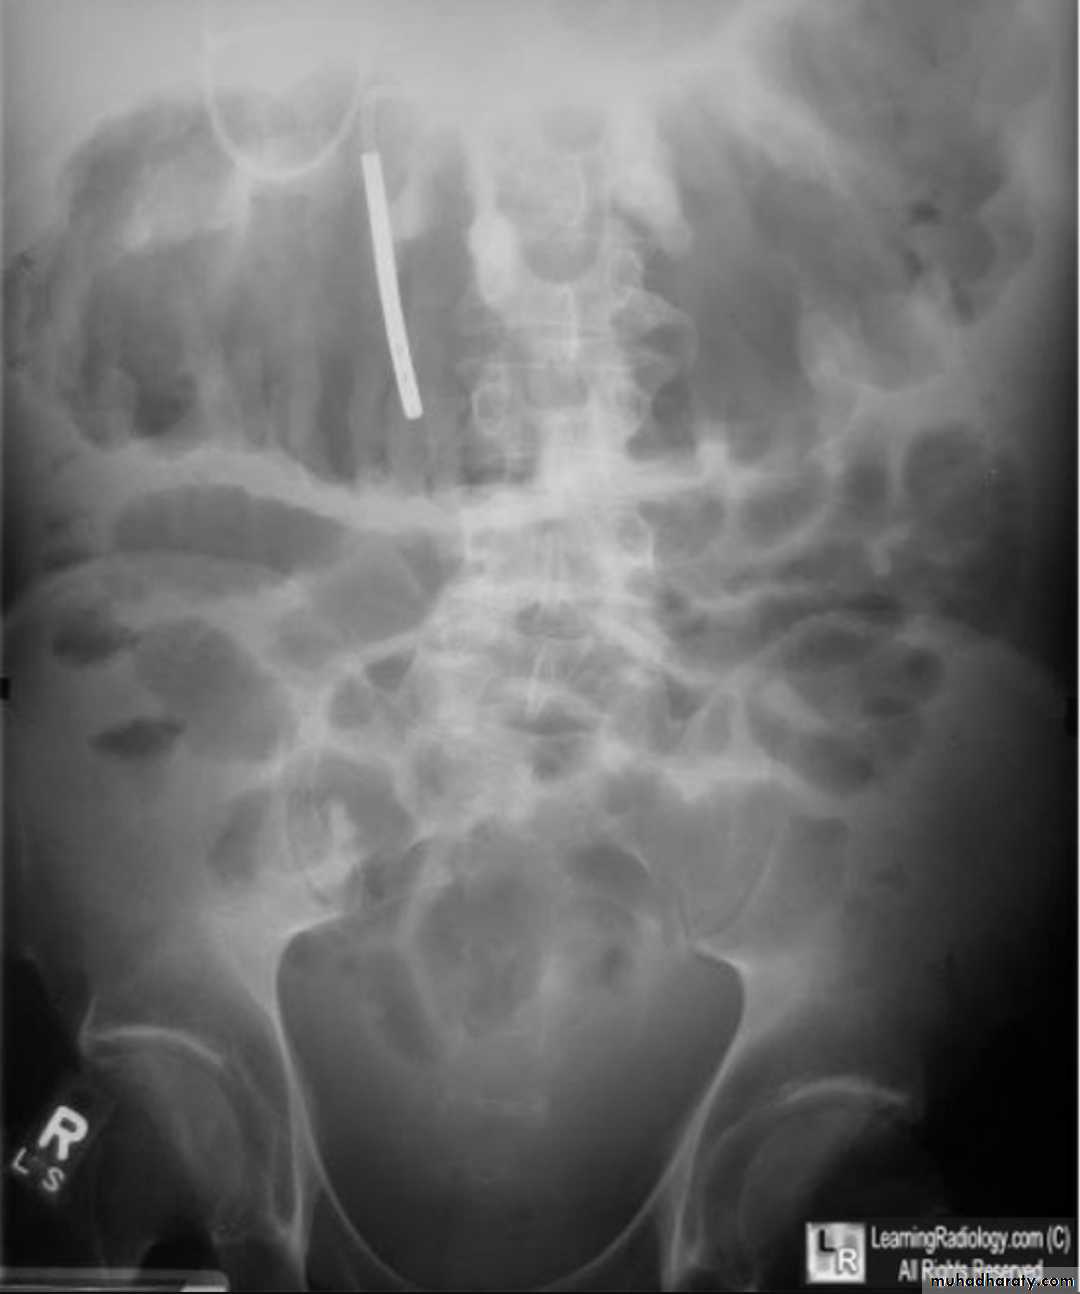

Small bowel obstruction accounts for 80% all mechanical intestinal obstruction; the remaining 20% result from large bowel obstruction

Radiographic features

Abdominal radiograph

Abdominal radiographs are only 50-60% sensitive for small bowel obstruction .

In most cases, the abdominal radiograph will have the following features:

dilated loops of small bowel proximal to the obstruction

predominantly central dilated loops

three instances of dilatation over 3 cm

valvulae conniventes are visible

fluid levels if the study in erect position